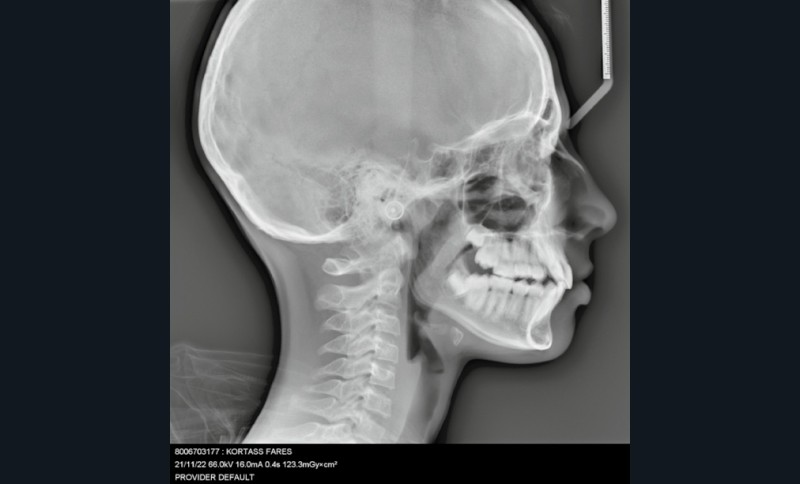

Sur le plan esthétique : profil orthofrontal, visage équilibré (fig. 1a).

Sur le plan squelettique : Classe II, schéma hypodivergent (fig. 1c). Sur le plan fonctionnel : aucune dysfonction ni parafonction.